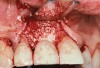

The importance of establishing periodontal health prior to both implant placement and the treatment of peri-implantitis has been discussed in numerous studies.22,28,29 In addition, properly contoured restorations on implants are essential in allowing a patient to maintain good plaque control following any surgical intervention. This may entail removal of an ill-fitting or poorly contoured crown and creating a well-fitting provisional prior to surgery (Figure 2 and Figure 3). In a study of 23 subjects who presented for treatment of peri-implantitis, it was reported that 74% of their implants diagnosed with peri-implantitis were associated with no accessibility/capability for proper oral hygiene. The authors emphasized the importance of proper prosthetic constructions that allow accessibility for oral hygiene around implants.30 Patients should also be taught proper homecare methods prior to surgery, to minimize plaque accumulation during and following treatment to ensure optimum healing of the peri-implant tissues.

Figure 3  Radiograph of the poorly contoured implant restoration in Figure 2.

Figure 3